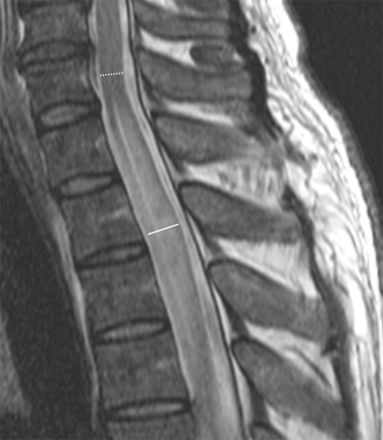

Radiologists were blinded to all patient and clinical data. Cervicomedullary junction involvement was defined as the main or separate lesion involving the uppermost cervical spinal cord at the level of the medulla oblongata. An imaginary line connecting the inferior cortex of the C1 anterior and posterior arches on sagittal T2WI was used as the lower border (Fig 1), and the pontomedullary junction was used as an upper border. Cord expansion was independently measured on sagittal T2WI by 2 radiologists with 5 and 3 years of experience, respectively. Values were averaged for the analysis. Only MR images obtained during the acute/early stage of disease (within 2 months of onset)12 were used for measurement. The ratio of cord expansion was measured as the anteroposterior diameter of the most swollen spinal cord segment to the anteroposterior diameter of the noninvolved spinal cord in the cranial direction on sagittal T2WI (Fig 2). The diameters were measured in millimeters to an accuracy of 1 decimal digit. If LETM extended to the level of the foramen magnum, the ratio was not useful for representing cord expansion due to an anatomic increase in the anteroposterior diameter of the medulla oblongata; thus, ratios were not measured in such cases. Ratio values were dichotomized with a cutoff value to maximize the sum of the sensitivity and specificity.

Sagittal T2-weighted spinal MR imaging of a 43-year-old man with LETM. Cord expansion ratio is measured as the anteroposterior diameter of the most swollen spinal cord segment (solid line) to the anteroposterior diameter of the noninvolved spinal cord in the cranial direction (dotted line). Two independent readers measured the cord expansion ratio as 1.65 and 1.71.